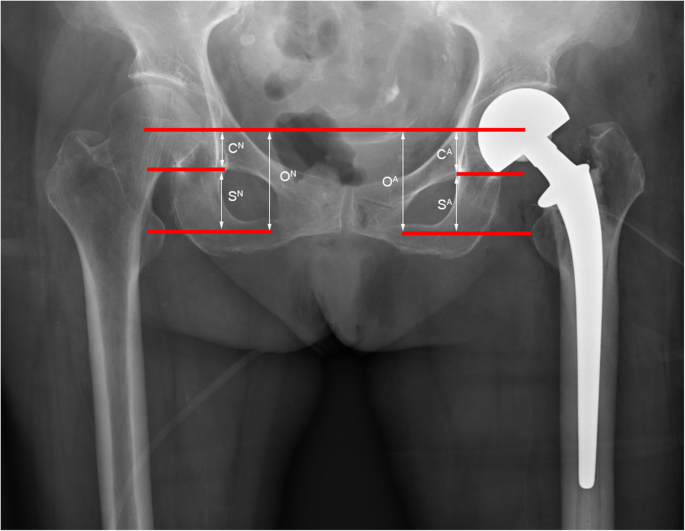

According to the postoperative pelvic orthographic X-ray (scale bar = 120; pixels = 1 cm), the drawing tool (Photoshop) was used to evaluate the unequal length of the lower limbs by the CFR-T-LT method, as described by Anthony et al. [14] (Fig. 4). An initial reference line is drawn between the centers of femoral rotation, and two further lines are drawn parallel to it. The first is at the level of the most inferior part of the acetabular teardrop to give measurement C, which corresponds to any inequality (CA-CN) due to the position of the cup. The second is at the level of the center of the lesser trochanter to give measurement S, which corresponds to inequality (SA-SN) due to the position of the stem. The sum of the two is measurement O which corresponds to the overall LLD (OA-ON).

According to the postoperative X-ray, the drawing tool (Photoshop) was used to evaluate the unequal length of the lower limbs by the CFR-T-LT method. An initial reference line is drawn between the centers of femoral rotation, and two further lines are drawn parallel to it. The first at the level of the most inferior part of the acetabular teardrop to give measurement C, which corresponds to any inequality (CA-CN) due to the position of the cup. The second is at the level of the center of the lesser trochanter to give measurement S, which corresponds to inequality (SA-SN) due to position of the stem. The sum of the two is measurement O which corresponds to the overall leg length inequality (OA-ON)